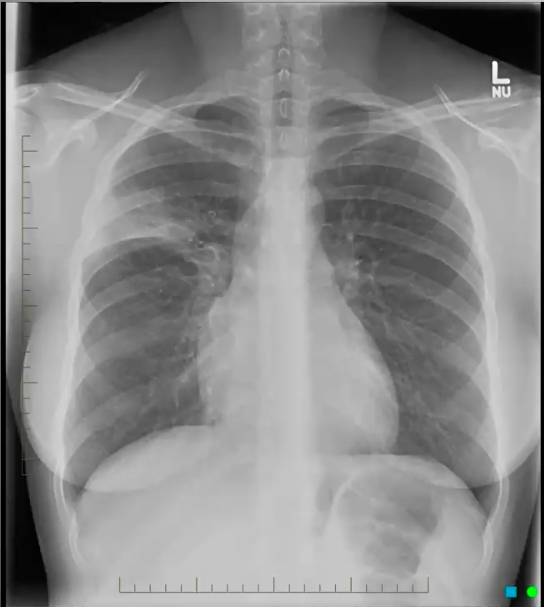

What’s your diagnosis?

Left lingula pneumonia because loss of left heart border (silouhette sign)